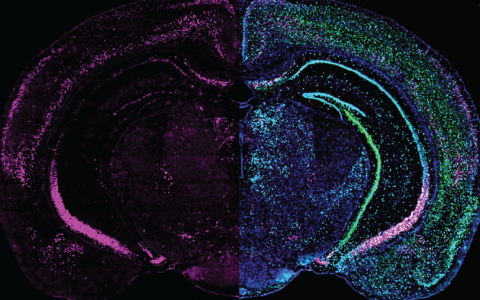

Brain slice showing projections in yellow, pink and blue

Coronal brain slice showing projections from different visual areas in the cerebral cortex to the ventrolateral geniculate nucleus (vLGN). These pathways are part of the circuit identified as mediating the suppression of instinctive fear responses.